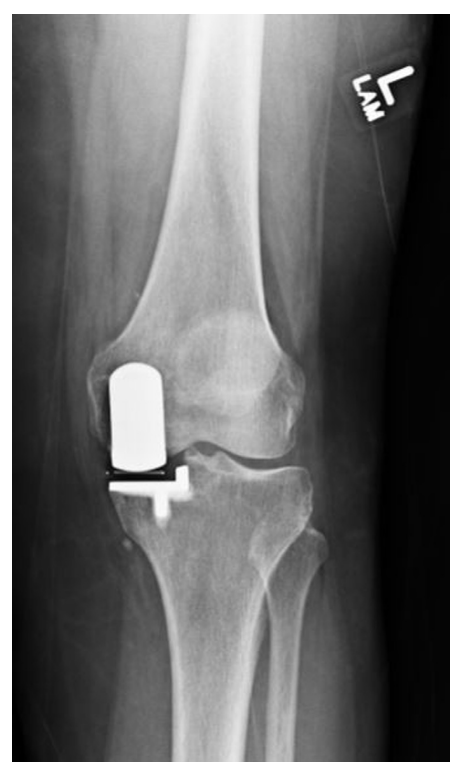

Kozinn和Soctt的经典限制性纳入标准在现代研究中得到了极大的扩展,这些研究表明UKA在年轻患者、肥胖患者、髌股疾病患者以及那些非常活跃的患者中取得了成功。无论如何,正确的患者选择对于确保UKA的成功结果仍然至关重要。对于所有前内侧OA(图1)、畸形可纠正(图2)、膝关节韧带完好、膝关节活动范围保留、屈曲挛缩小的患者,都可以考虑内侧UKA。

图2:(A)站立正位X线片显示内侧关节间隙丢失。(B)外翻应力X线片显示可矫正的对齐和对侧关节空间的保存。